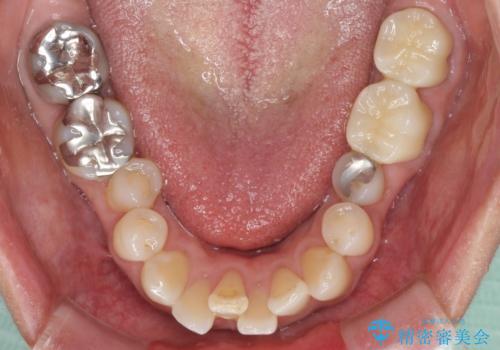

上の奥歯は一部神経を取り除くこととなりましたが、残った神経は正常な状態を保つことができました。

下の奥歯も、虫歯を取り除いて仮歯を装着したことで歯肉の腫れが引き、出血することもなくなりました。